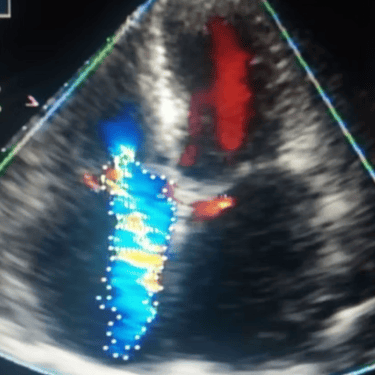

El Ecocardiograma ofrece imágenes del corazón en movimiento y tiempo real.

Mediante ultrasonido, la ecocardiografía aporta información acerca de:

Funcionamiento de las válvulas cardiacas.